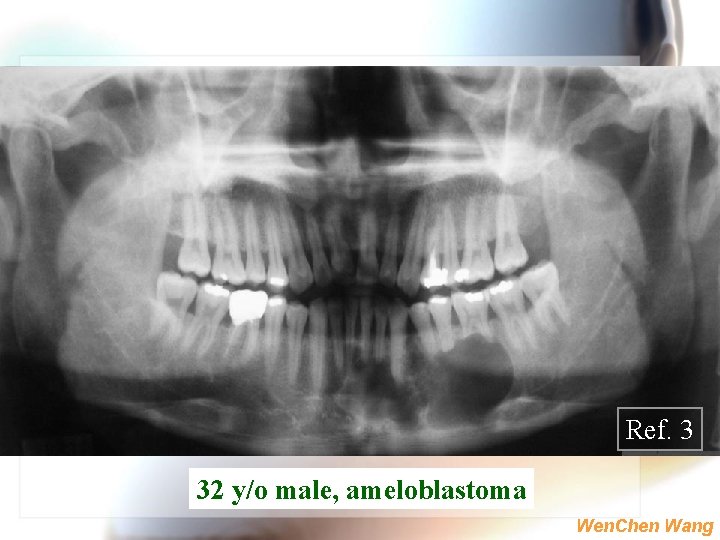

Ref. 3 32 y/o male, ameloblastoma Wen. Chen Wang

Ameloblastoma-conventional type | | | Wide age range, mean=39 y/o, rare in young children > 80% in mandible, molar-ramus Painless swelling or expansion the bone, benign but local invasive non-encapsulated and destructive seldom causes paresthesia may cause loosening of teeth or resorption Ref. 1 Ref. 2 Wen. Chen Wang